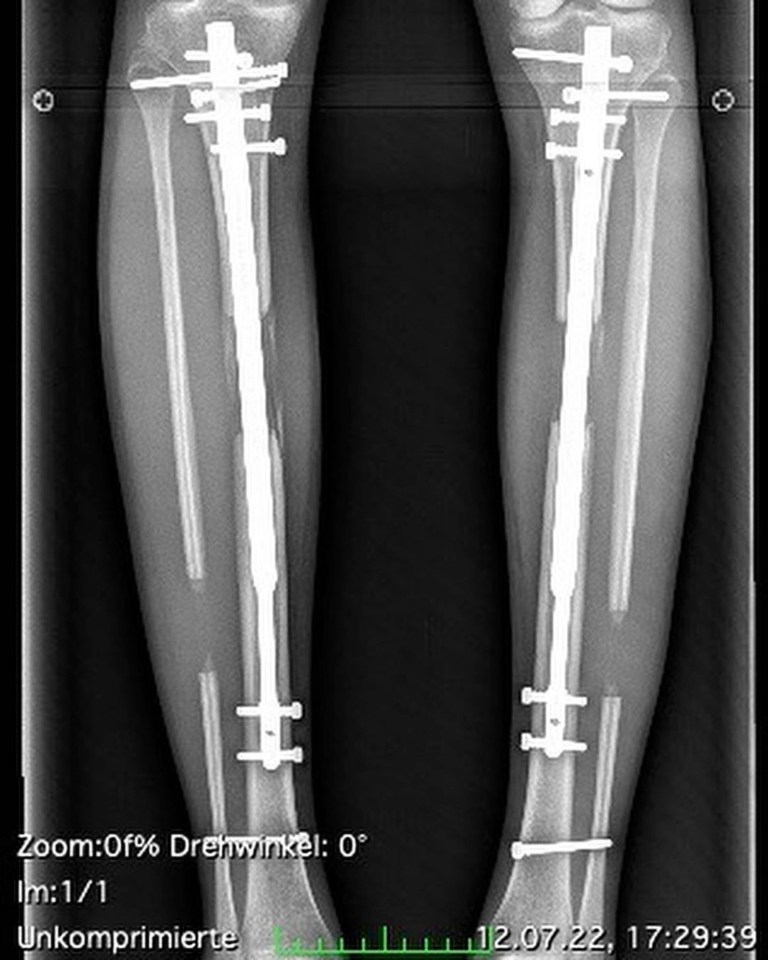

Cea mai utilizată operație pentru creșterea în înălțime se bazează pe metoda Ilizarov, dezvoltată în anii ’50 în Siberia: osul este secționat și alungit treptat cu fixatori externi, stimulând regenerarea oaselor, tendoanelor, nervilor și vaselor.

Variantele moderne includ metoda Lon, care folosește șuruburi intramedulare și fixatori externi ulterior îndepărtați, și Precice 2, mai scumpă, dar mai puțin invazivă, controlată prin telecomandă, reducând cicatricile și riscul de infecție.